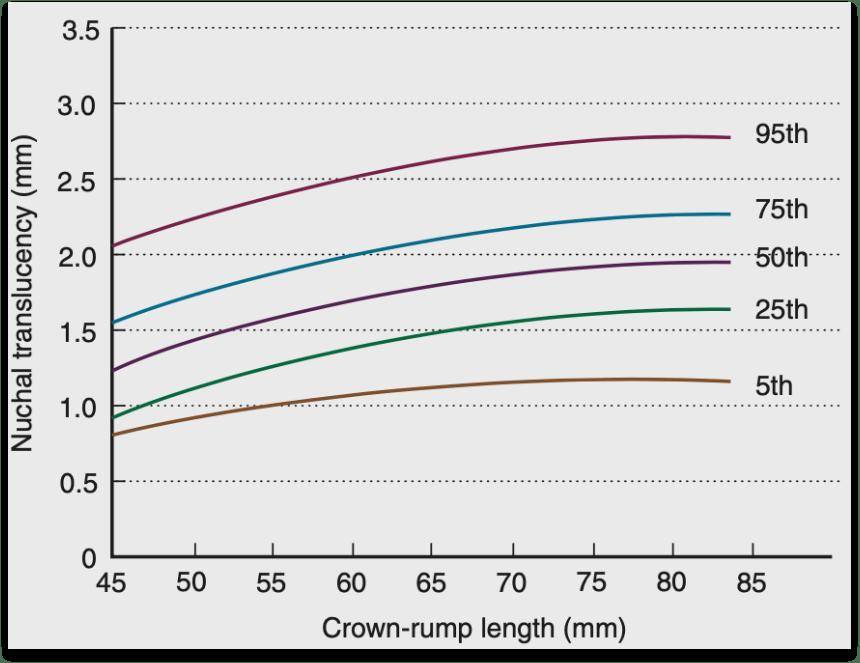

NT 的參考值不是固定的,會跟著胎兒頭臀徑的增長而變化,判斷標準是:厚度大於對應頭臀徑 NT 值的第 95 百分位數,認為存在NT增厚收藏。NT增厚數值越大,通常風險越高。

圖片來自Creasy and Resnik’s Maternal-Fetal Medicine PRINCIPLES AND PRACTICE 7THEdition